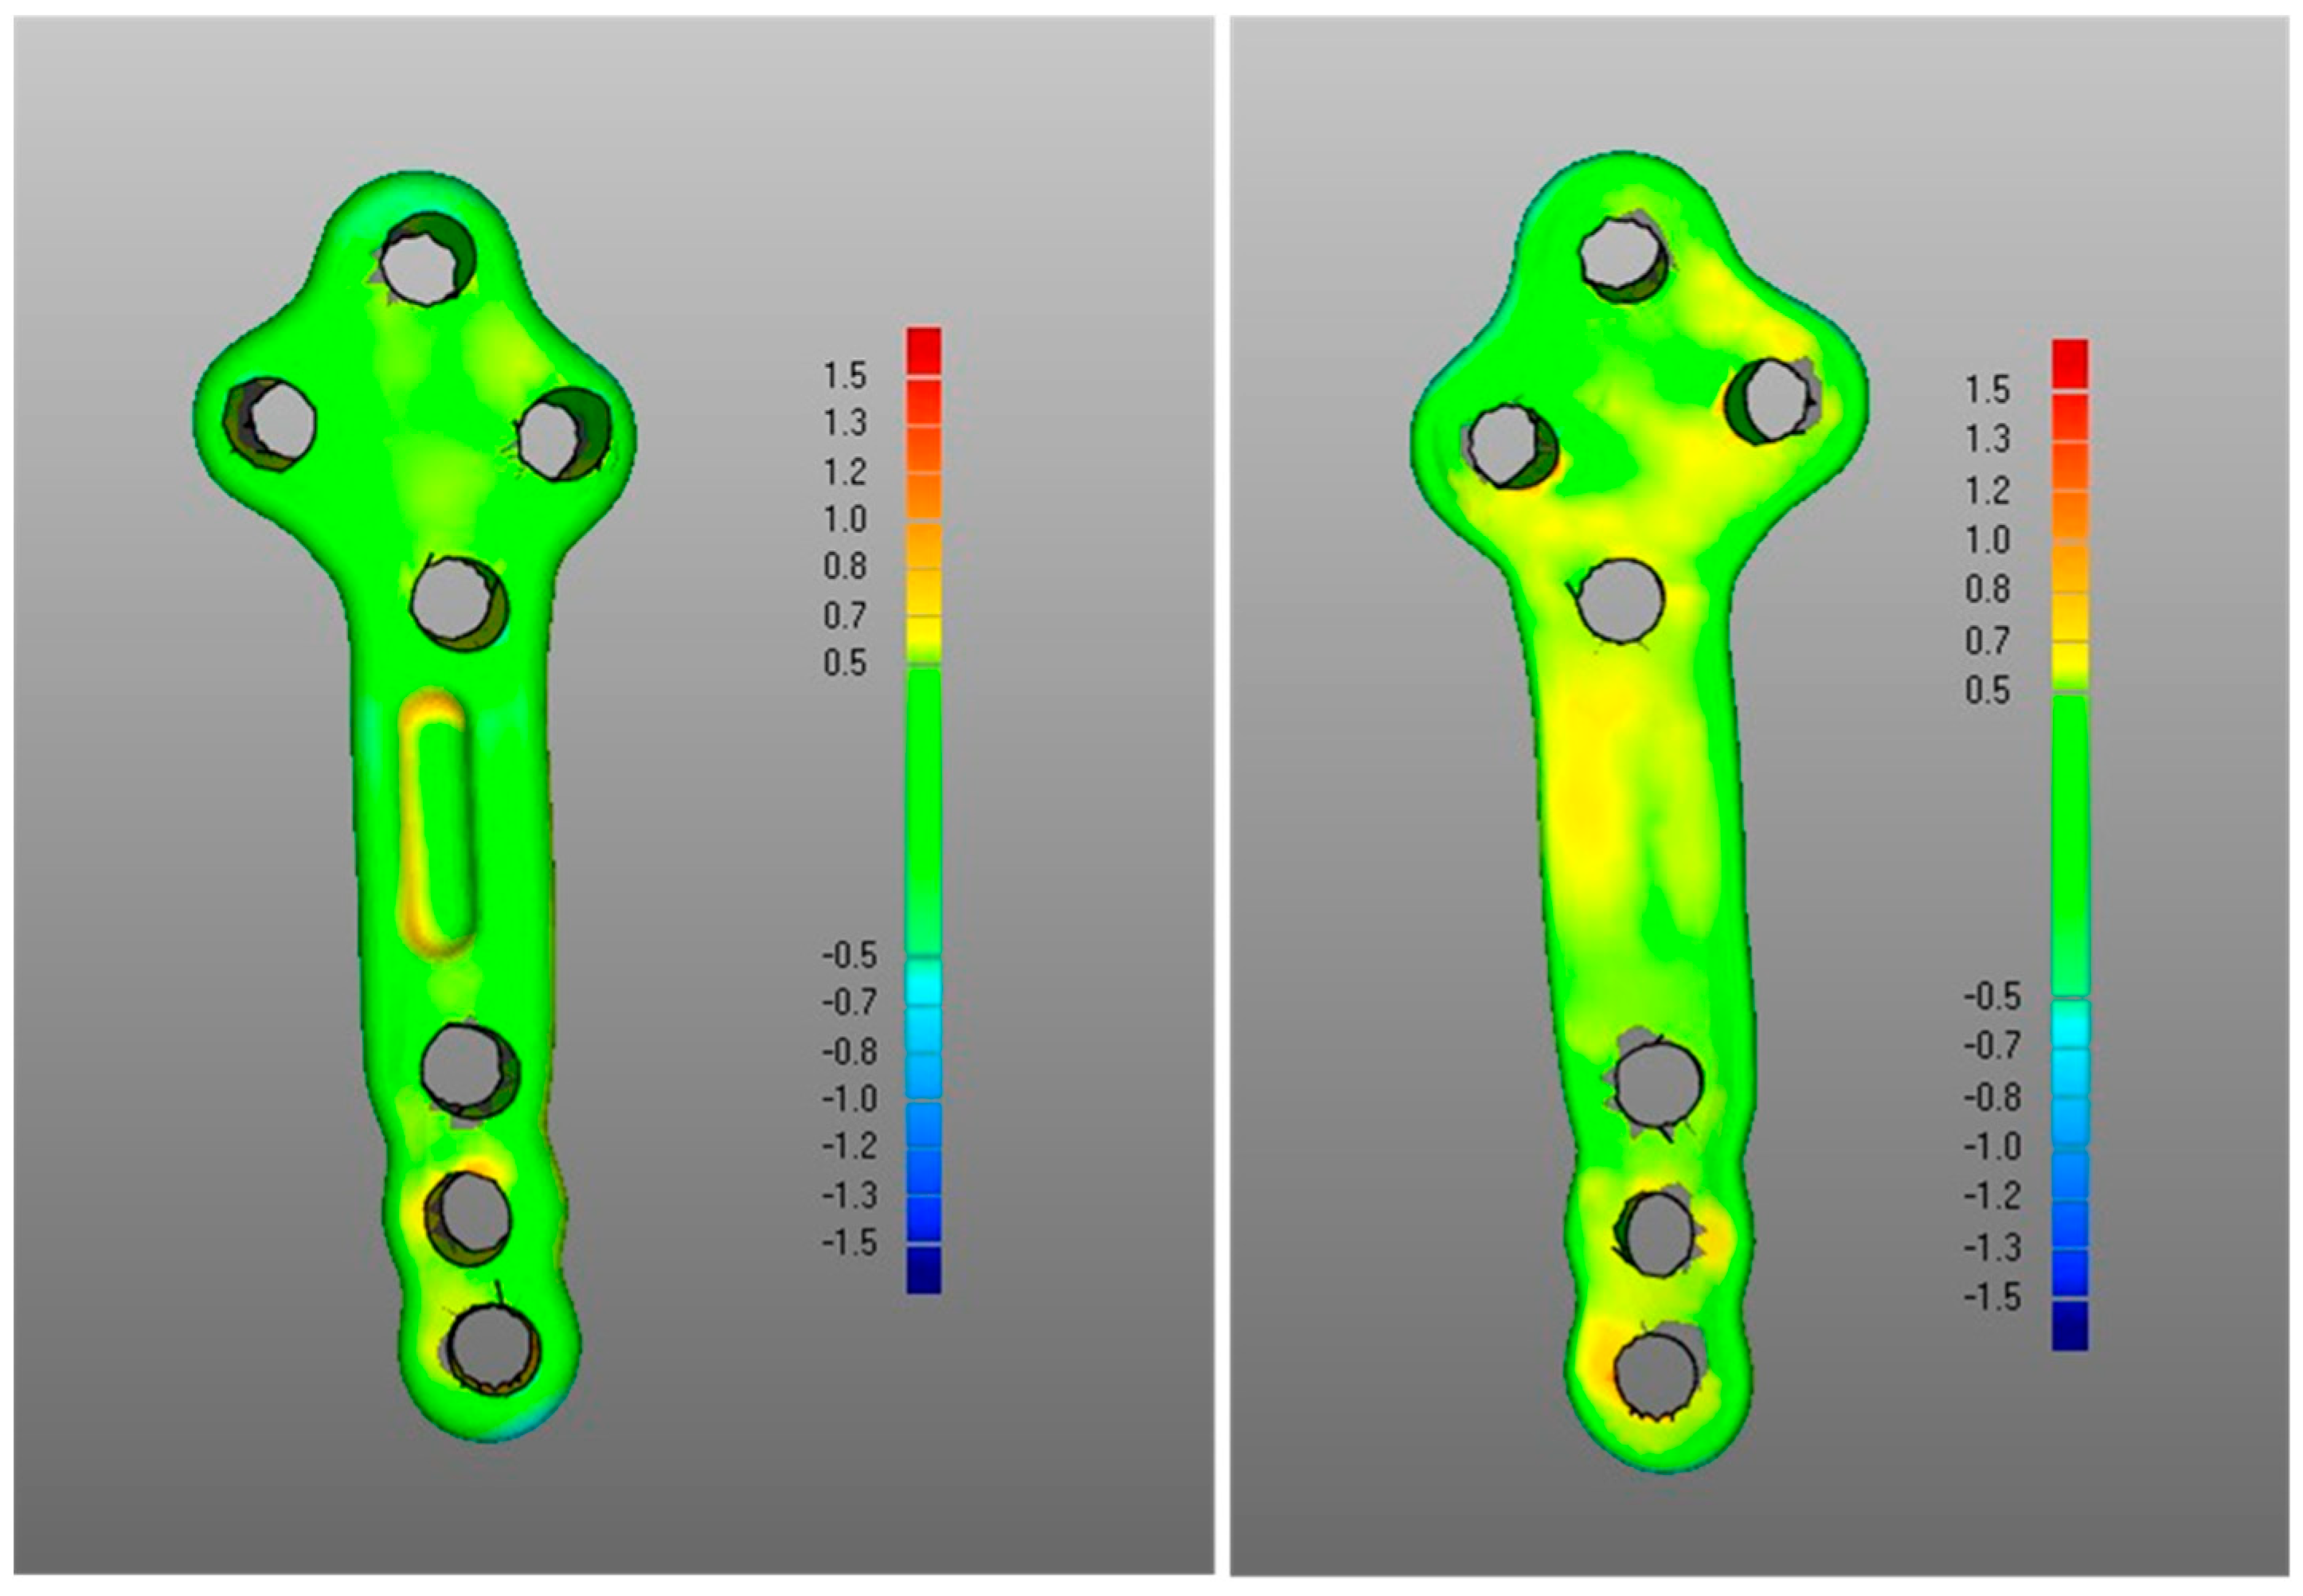

- The DMA values associated with the deformation of the fixation plate (average for was 0.4 mm, was −0.2 mm, with DSD of 0.4 mm) were all less than the critical value, i.e., 1 mm (Table 1) and with most of the points in the safety zone (Table 2), indicating that the overall shape of the metal plate was maintained after surgery at follow-up (Figure 3 and Figure 5).

- Regarding the matching of the plate surface contour to the tibia, the comparison between PLA, i.e., iii-a (Figure 6 left), and POST, i.e., iii-b (Figure 6 right), the low DMA values (Figure 3 and Table 1) reveal a very good replication of the planned contour matching of the plate to the tibia in the POST condition. In iii-a comparison, there was no negative value, i.e., penetration, of the test surface relative to the reference (Table 2).